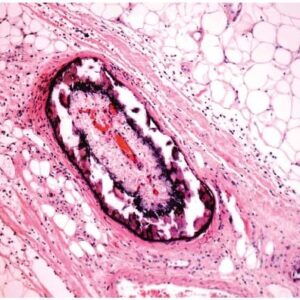

- کیست گوش میانی (کلستئاتوم). اگرچه این کیست بسیار نادر است، اما این کیست که از سلول های پوستی و سایر مواد زائد تشکیل شده است، می تواند در نتیجه طولانی مدت پارگی پرده گوش در گوش میانی ایجاد شود.

- زباله های مجرای گوش معمولاً با کمک جرم گوش محافظ گوش به گوش خارجی می روند. اگر پرده گوش پاره شود، بقایای پوست می توانند به گوش میانی رفته و کیست تشکیل دهند.

- کیست در گوش میانی محیطی دوستانه برای باکتری ها فراهم می کند و حاوی پروتئین هایی است که می تواند به استخوان های گوش میانی آسیب برساند.